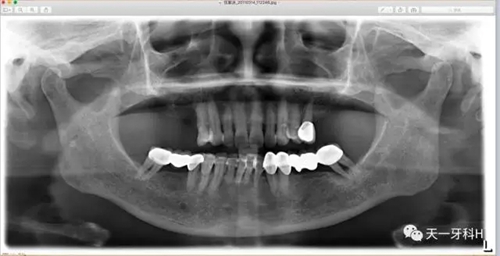

2011年3月3日拍攝:

2011年3月3日,這個患者又來到了診所,此時的她上頜的烤瓷橋已經沒有了,做基牙的牙齒右上七和右上五沒有了,右上四遠中的牙槽骨也已經破壞到根尖四分之一了,左上八沒有了,只剩下左上五,下頜烤瓷橋雖然還在,但左下八近中的牙槽骨吸收也到達根尖了。

15 的牙槽骨破壞已經到達根尖,這樣的牙齒就是無法保留的牙齒,只能拔掉?;仡^看2004年的15,盡管有牙周膜間隙的改變,如果當時患者聽從勸導,拆除烤瓷橋保住15號牙是毫無懸念的。我不知道這個病例的發(fā)生、發(fā)展過程

能否讓你們醒悟,牙周病患者做烤瓷牙要慎之又慎!